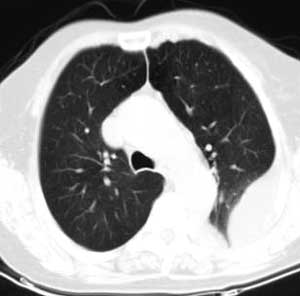

测ct值3-6hu,

既然ct值是3-6hu,还不如考虑包裹性积液。

支持包裹性胸腔积液。

请上传纵隔窗。目前还是支技包裹性积液(明显梭形),即使是间皮瘤并积液也少梭形的。

从图片看,包裹性积液好象更合理,梭形,ct值3-5hu(在哪看到的?);胸膜间皮瘤如此规则,不多见。

左侧背部胸膜肥厚,伴包裹性积液,不考虑间皮瘤.